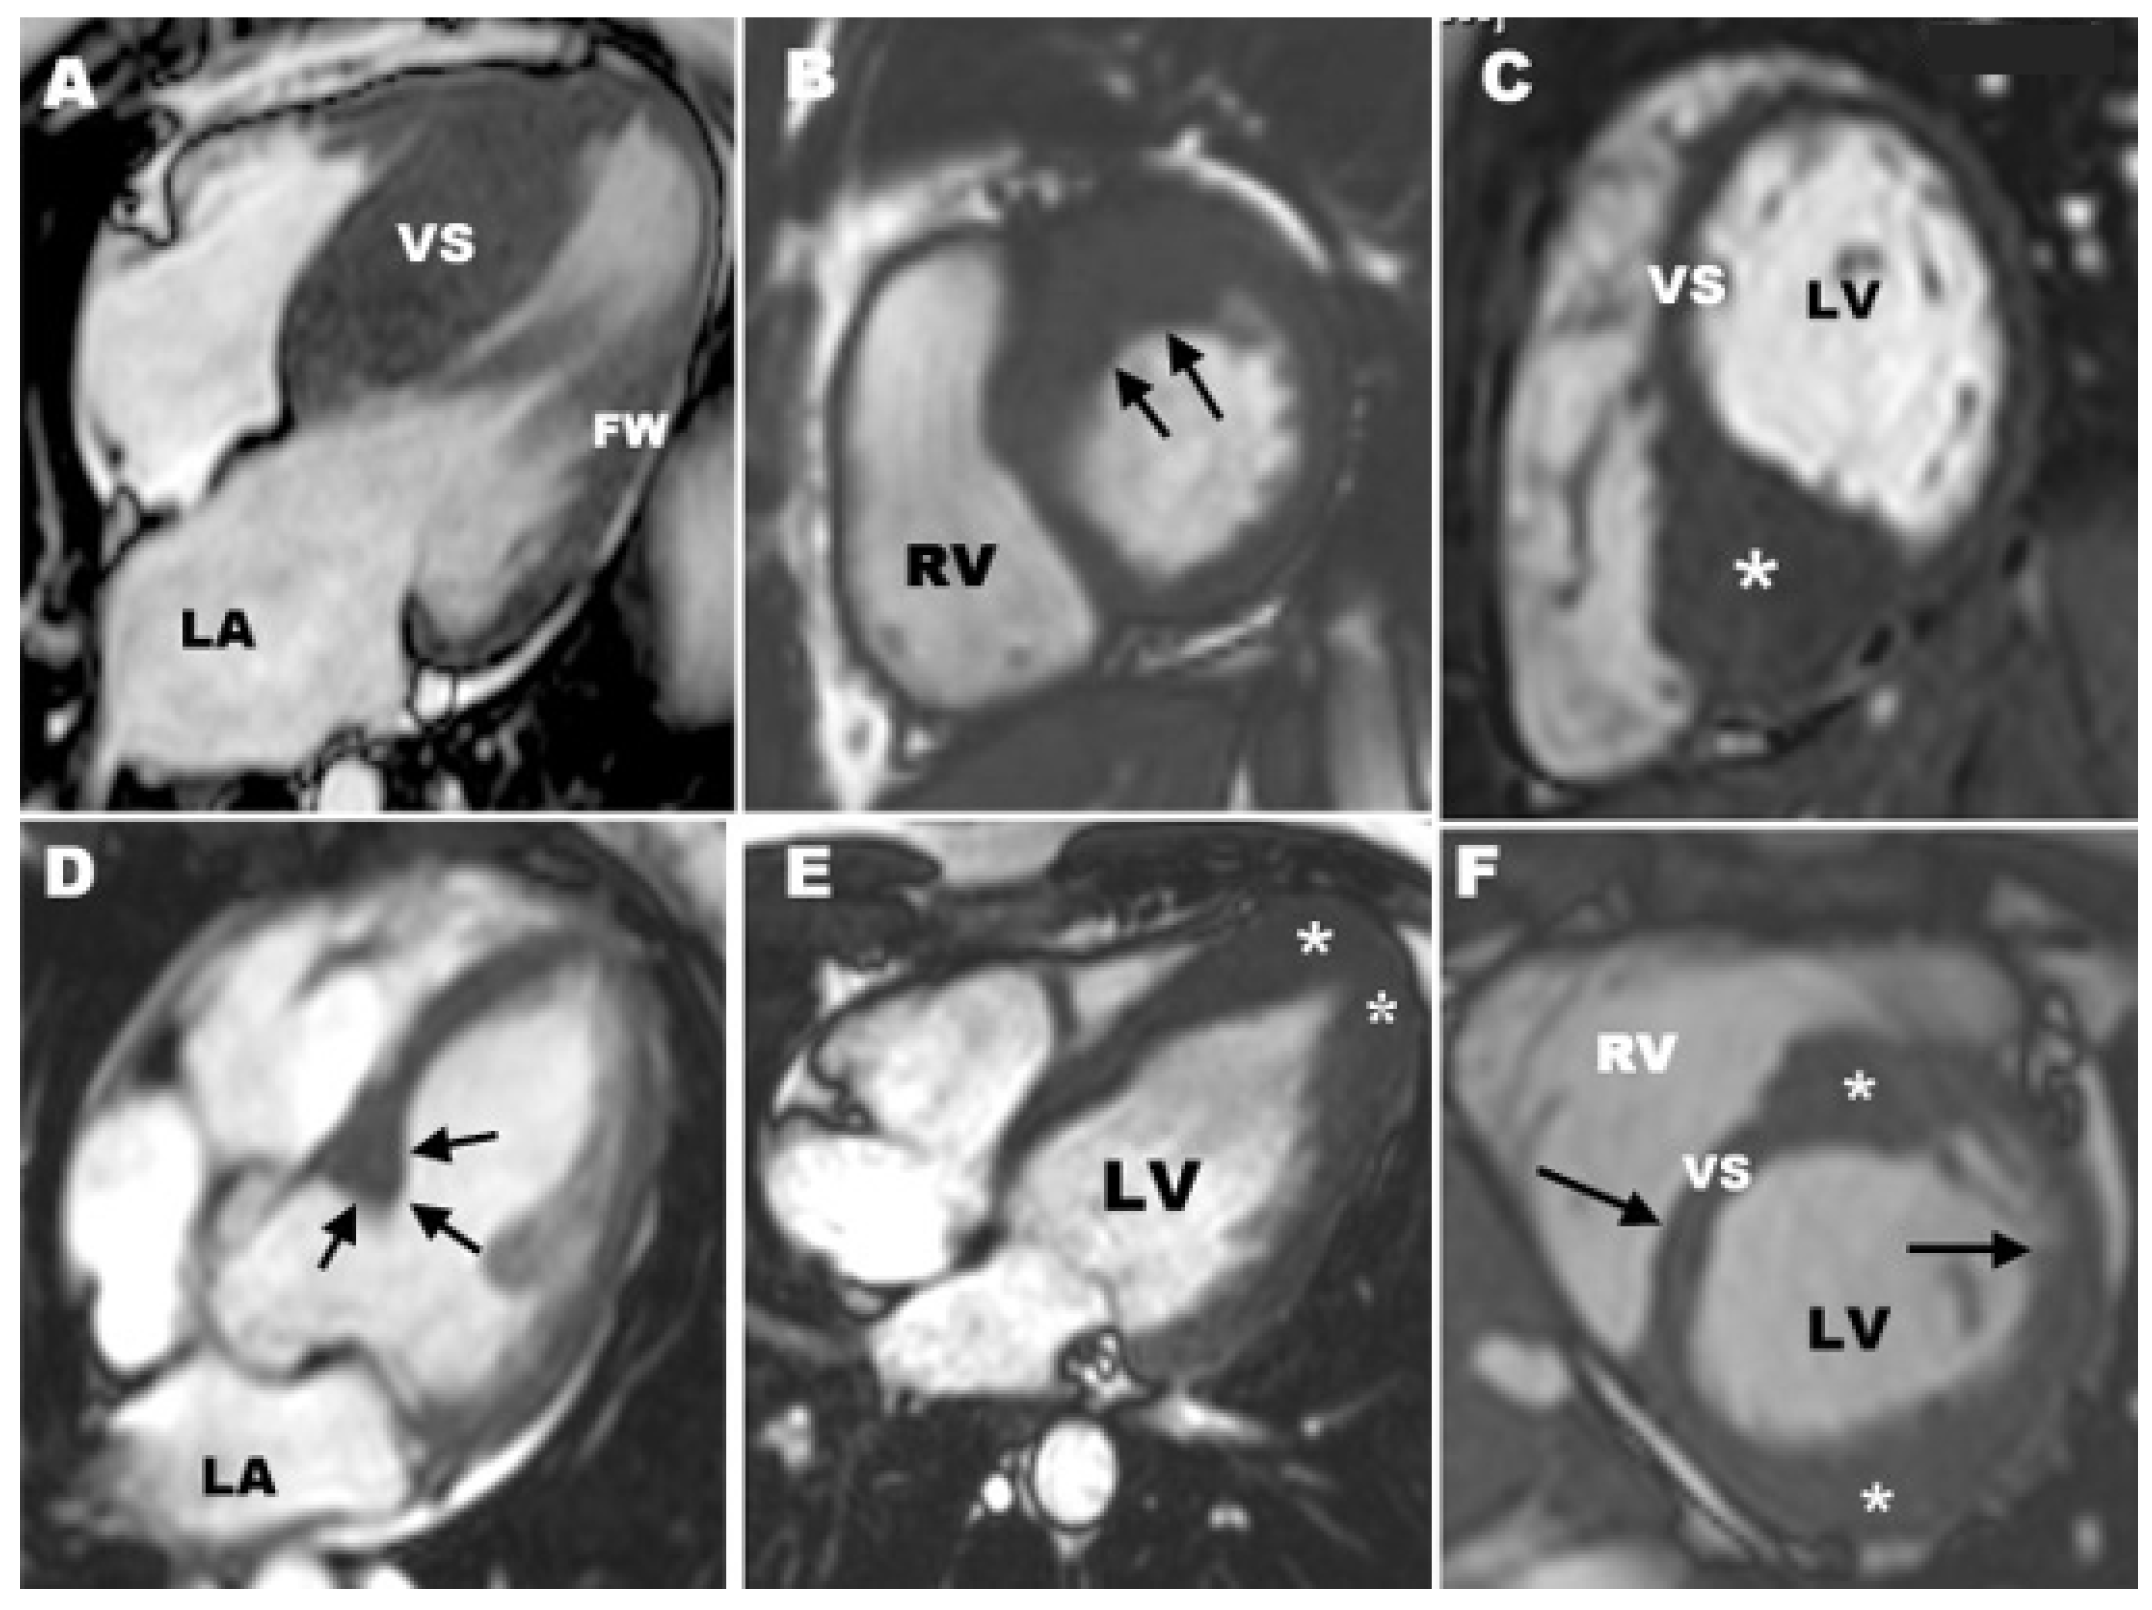

3. Cardiac MR for HCM

3.1. CMR Evaluation of Apical Hypertrophic Cardiomyopathy

3.2. CMR Evaluation of Focal Hypertrophic Cardiomyopathy

3.3. CMR Evaluation of Midventricular Obstruction

3.4. CMR Evaluation of Apical Aneurysm

3.5. CMR Evaluation of LVOT Obstruction

3.6. CMR Evaluation of Mitral Valve and Papillary Muscles